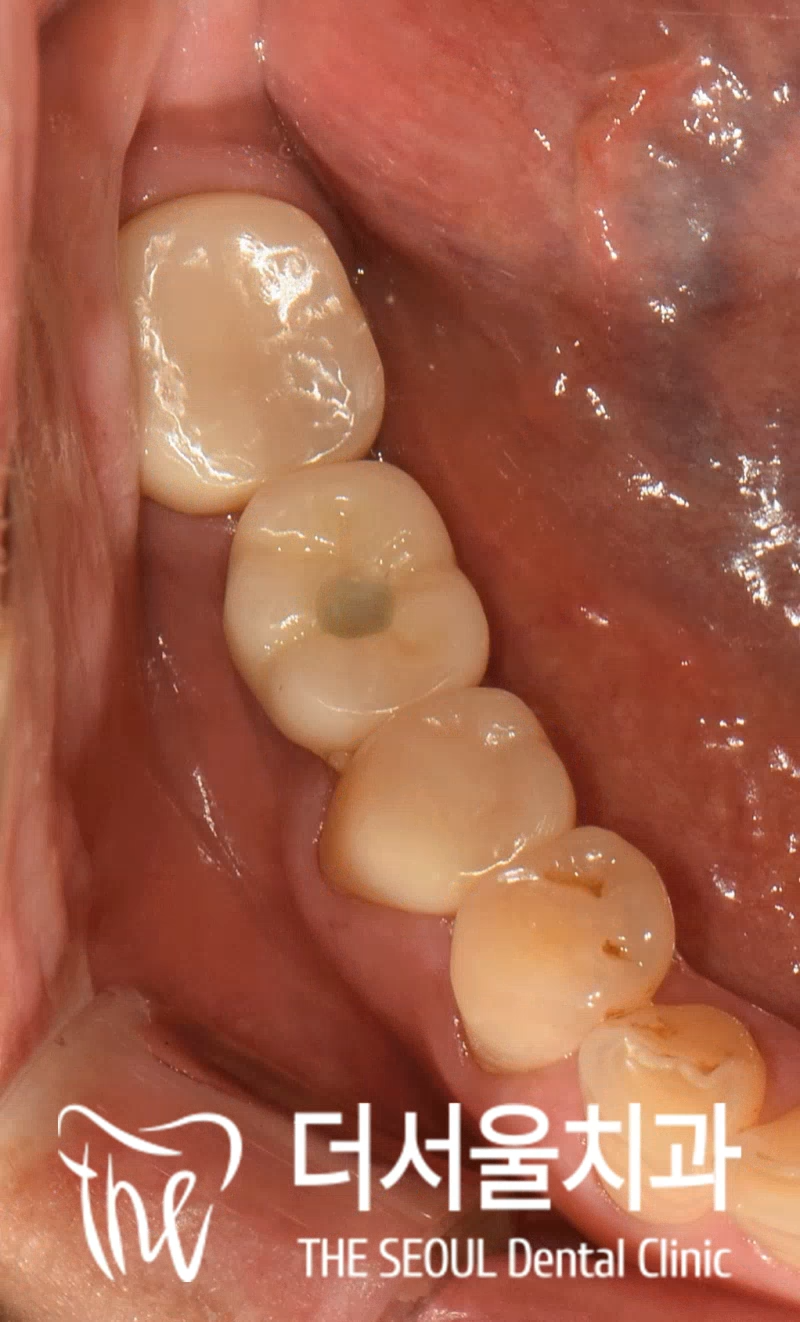

치근 파절 이란? 치아 뿌리 쪽에 형성된 파절 로 영어로는 ‘Root facture’라고 합니다. 쉽게 말해 뿌리가 갈라진 상태로 발치